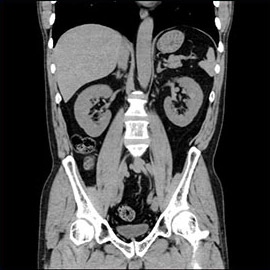

80列マルチスライスCTで撮影した画像

腹部

腹部(造影)